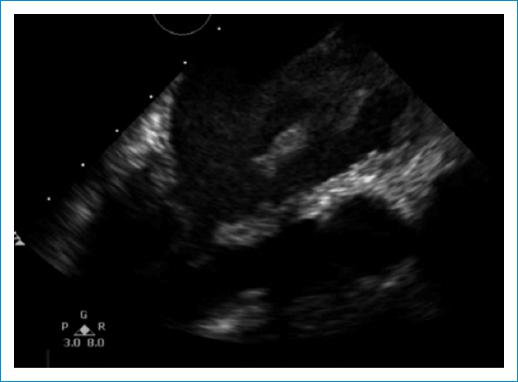

El electrocardiograma documentó único hallazgo de taquicardia sinusal. Entre los paraclínicos de ingreso se encontró INR en rangos terapéuticos (2.7) hipoalbuminemia, gases arteriales con evidencia de acidosis metabólica con anión Gap normal con hipoxemia moderada (Tabla 1) y radiografía de tórax simple con evidencia de edema pulmonar en fase intersticial (Fig. 1).Se complementó con ecocardiograma transtorácico, el cual reportó una masa en la aurícula izquierda, que parecía estar adherida a su pared posterior y obstruía el tracto de entrada del ventrículo izquierdo (Fig. 2). Fue valorada por el equipo de cirugía cardiovascular quienes indicaron la toma de ecocardiograma transesofágico, el cual permitió una mejor caracterización de la lesión; en este se halló una masa lobulada, de bordes irregulares, ecogenicidad intermedia y quistes en su interior, la cual se encontraba adherida a la parte posterior de la aurícula izquierda y a la vena pulmonar inferior derecha a través de un pedículo, comprometiendo el flujo de dicho vaso e infiltrando también su pared (Fig. 3). Esta masa protruía, también, a través del tracto de entrada del ventrículo izquierdo (Fig. 4), comprometiendo el flujo de manera significativa (velocidad pico: 2,5 m/s y gradiente medio de 14 mm Hg). Adicionalmente, el septum interauricular se encontraba tapizado por una masa de similares características (Fig. 5). A razón de dichos hallazgos, fue sometida a intervención quirúrgica, en la que se halló una masa multilobulada de características sarcomatosas de 8 cm x 4 cm con infiltración completa de la vena pulmonar derecha y oclusión del 100% de su luz; la infiltración de las paredes y la extensión hacia el hilio pulmonar hicieron imposible una resección radical, con reporte histopatológico de sarcoma indiferenciado (Fig. 3).

Figura 3 Ecocardiograma transesofágico en el que se aprecia masa lobulada de ecogenicidad intermedia y quistes en su interior, adherida al aspecto posterior de la aurícula izquierda.